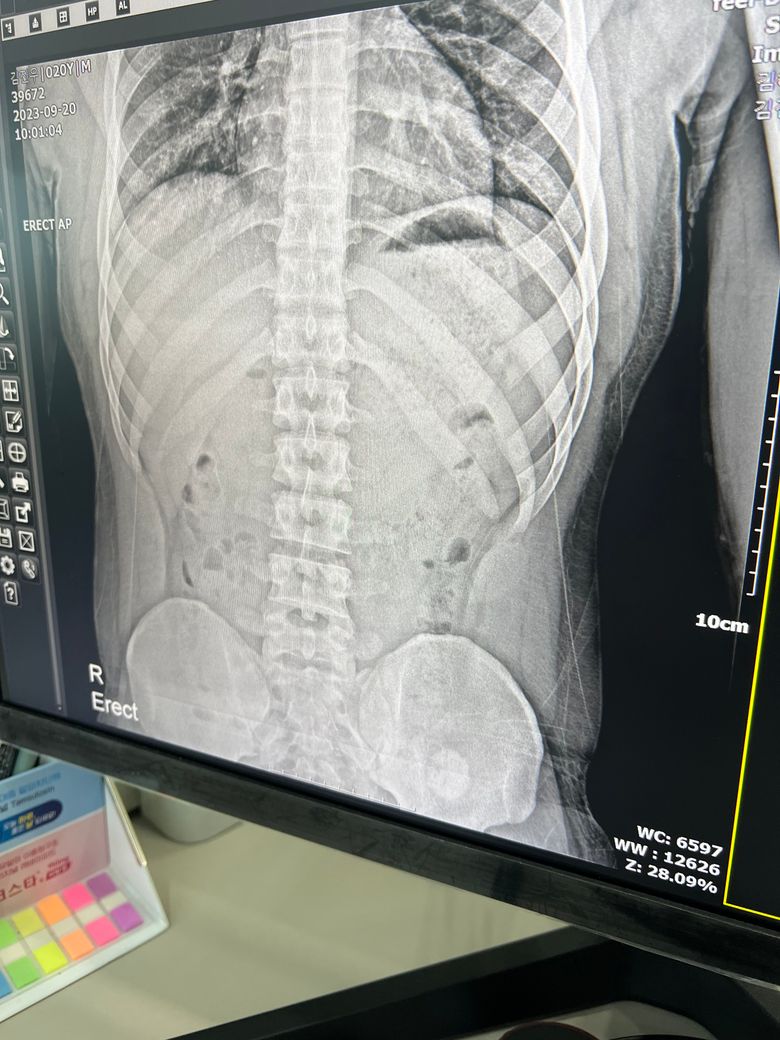

우연히 엑스레이를 찍다 골반에서 뭐가 발견됐습니다

골반 쪽에 동그란 원 형태로 있습니다

아프거나 통증은 없고 우연히 발견했습니다

엑스레이에서 우연히 발견된 덩이에 대해 걱정스러우시지요. 추가적인 엑스레이 촬영이나 CT 촬영으로 위치부터 파악해야 할 것으로 보입니다. 정형외과나 외과를 방문해보실수 있겠고 종합병원을 가시는 것이 타과 진료로 넘어갈 때 편하실 것으로 보입니다.